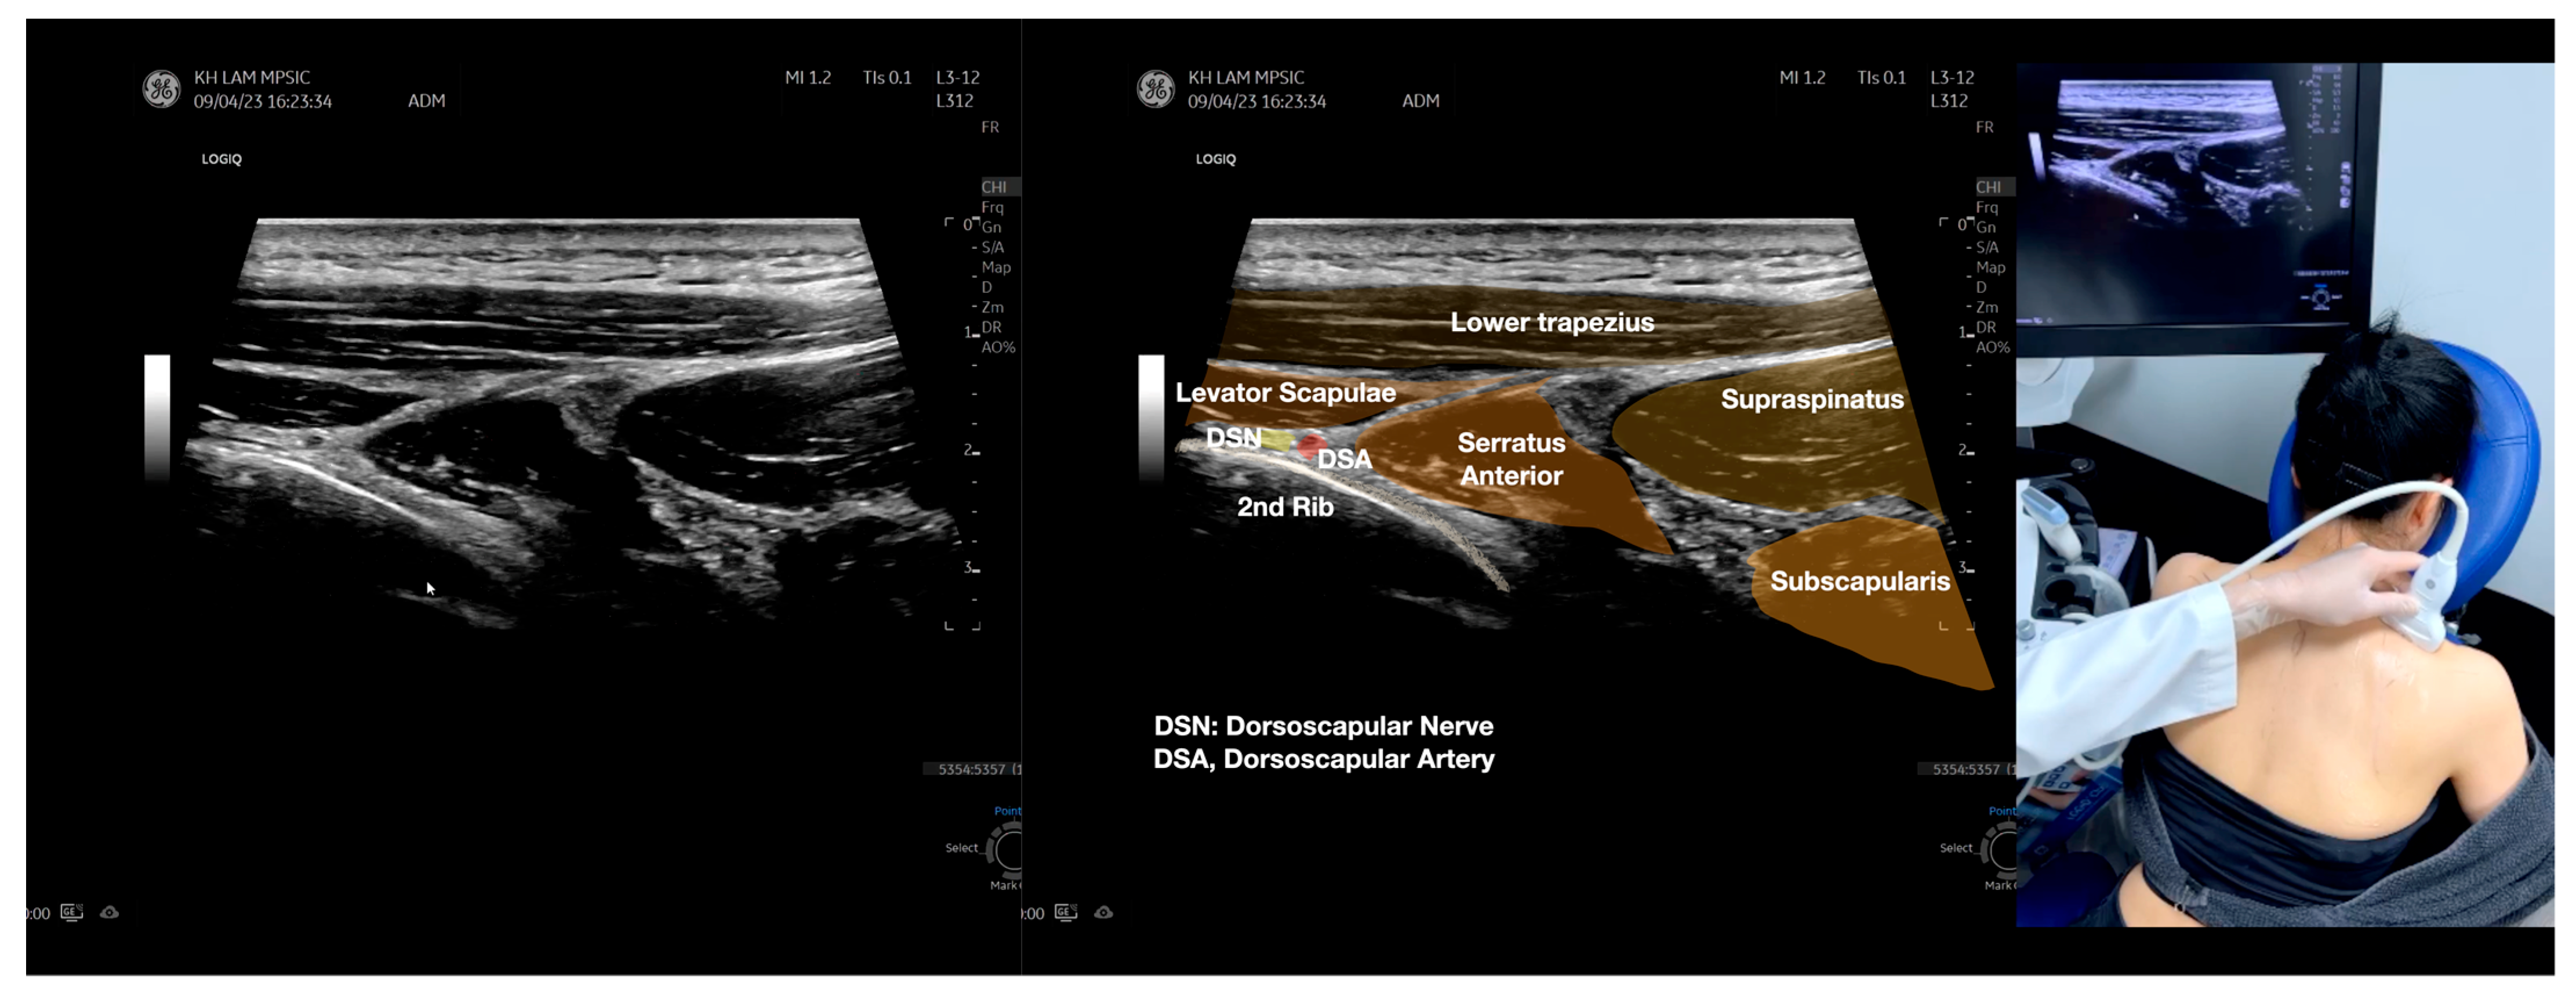

Figure 4.

Sonoanatomy of the medial edge of the scapula, its related muscles, and the infraspinatus fascia. The step-by-step scanning techniques of these structures illustrated in this figure have been shown in Video S8. Available online: https://www.dropbox.com/s/iaej3rxhl83kqt4/Figure%204.docx?dl=0 (accessed on 1 January 2023).